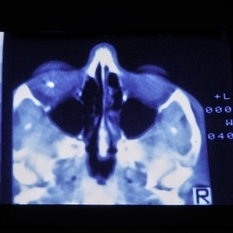

Jan 8 2015 by H. Michael Lambert, MD

Metal IOFB.

Condition/keywords: intraocular foreign body, trauma